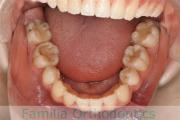

No.20V-499

- 主な症状:

- 上顎前突

- その他の症状:

- 叢生

- 年齢:

- 16歳

- 性別:

- 女性

- 抜歯部位

- 上:

- 44

- 下:

- 8558

- 主な使用装置:

- FEA

- 治療にかかった費用:

- 85万円

上の前歯が出っ歯気味なのを治したいということで来院されました。上下左右から小臼歯を抜歯して、歯科矯正用アンカースクリューを併用したマルチブラケット法により治療を行いました。動きの悪い歯やコントロールに苦労した場面があり、4年強・50回程度の通院が必要でした。

下顎前歯の叢生(でこぼこ、凹凸、ガタガタ)が著しく、後戻りのリスクが高い部位となります。